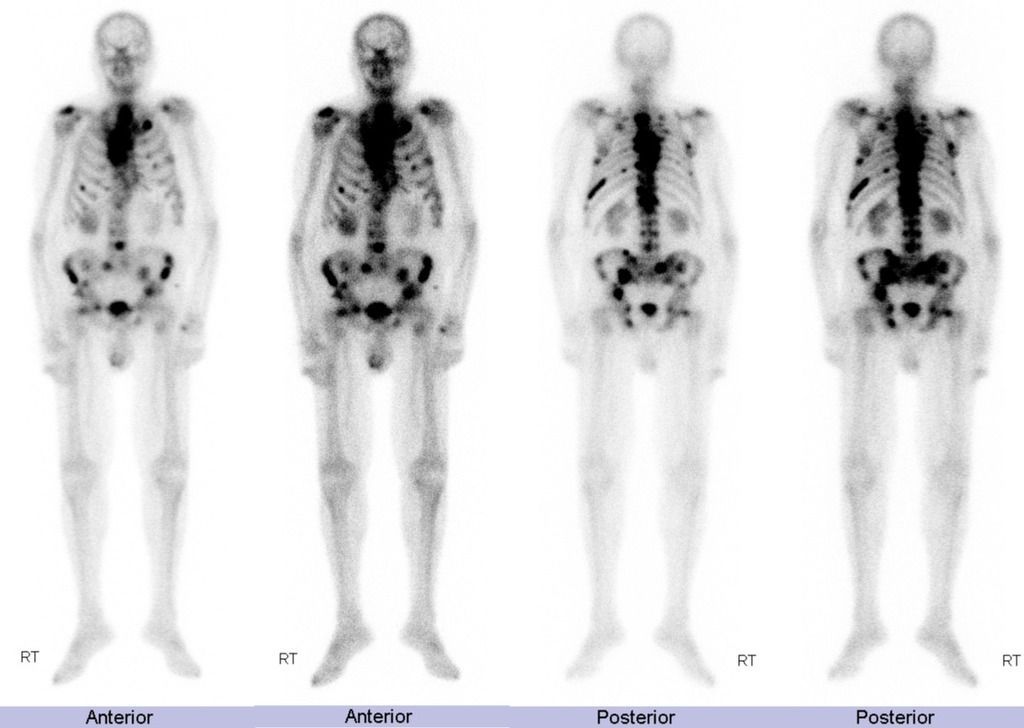

Following are the cancers that have tendency to metastasize to bone: - breast - lungs - prostate - kidney - melanoma - ovarian cancer - thyroid carcinoma Reference: https://www.cancer.org/treatment/understanding-your-diagnosis/advanced-cancer/bone-metastases.html#:~:text=Almost%20all%20cancers%20can%20spread,common%20site%20for%20bone%20metastases. Image via: https://radiopaedia.org/cases/metastatic-prostate-cancer-bone-scan?lang=gb